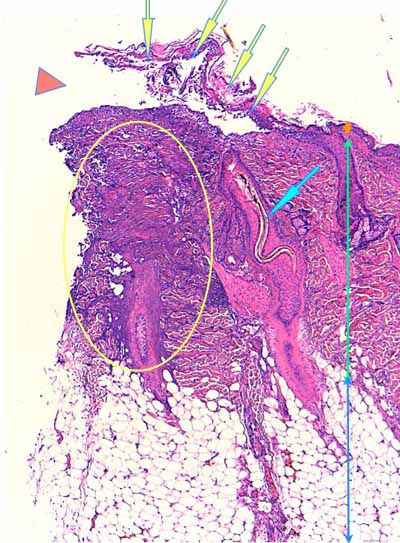

Photo 3 (Hémalun Eosine X 100) : l’épiderme se désengrène, une vésicule

sous-épidermique se forme. Le derme superficiel est œdémateux. Deux plages cellulaires dermiques

sont en étroit rapport avec des annexes folliculo-sébacées, dont une apparaît rompue.

Légendes de la Photo 3 :

- Ovales jaunes : plages cellulaires inflammatoires dans le derme périannexiel

- Flèche turquoise : follicule pileux rompu en rapport avec une plage inflammatoire

- Flèches jaunes : épiderme fragilisé qui se désengrène du derme

- Double flèche orange : épaisseur épidermique

- Double flèche verte : épaisseur dermique

- Double flèche bleue : épaisseur hypodermique

- Flèche orange : une vésicule sous-épidermique se forme